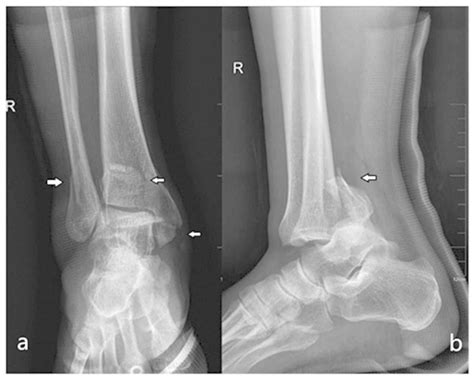

• X-rays: Standard radiographs to visualize the fracture pattern and the extent of displacement.

Diagnosing a *Pilon Bone Fracture* involves a combination of clinical examination and imaging studies. The initial assessment typically includes:

Diagnosis of Pilon Bone Fractures